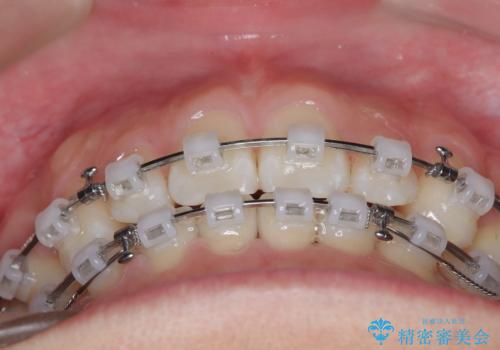

上下左右の第一小臼歯を抜歯し、クリアブラケット(白い装置)とメタルワイヤーを使用して矯正を開始。初期には犬歯のアーチ内への整列を優先し、中盤からは前歯と奥歯の咬合関係の調整を進めました。審美性に優れた装置を使用したことで、治療中も目立ちにくく、見た目へのストレスが少ない点も評価されています。全体の治療は1年半で完了し、見た目・噛み合わせともに大きく改善。患者本人も「短期間でここまで変わるとは思わなかった」と満足されていました。